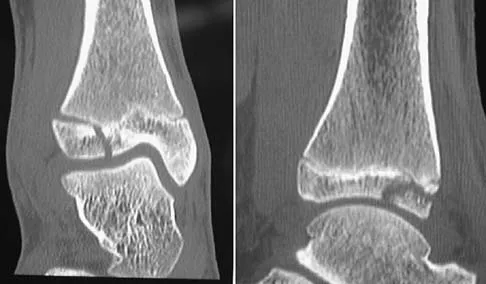

A 28-year-old man has had a 2-year history of progressive lateral ankle pain. History reveals that he underwent a triple arthrodesis at age 13 for a tarsal coalition. The pain has been refractory to braces, custom inserts, and nonsteroidal anti-inflammatory drugs. Weight-bearing radiographs of the ankle and foot are shown in Figures 3a through 3d. Surgical management should include which of the following?

Explanation